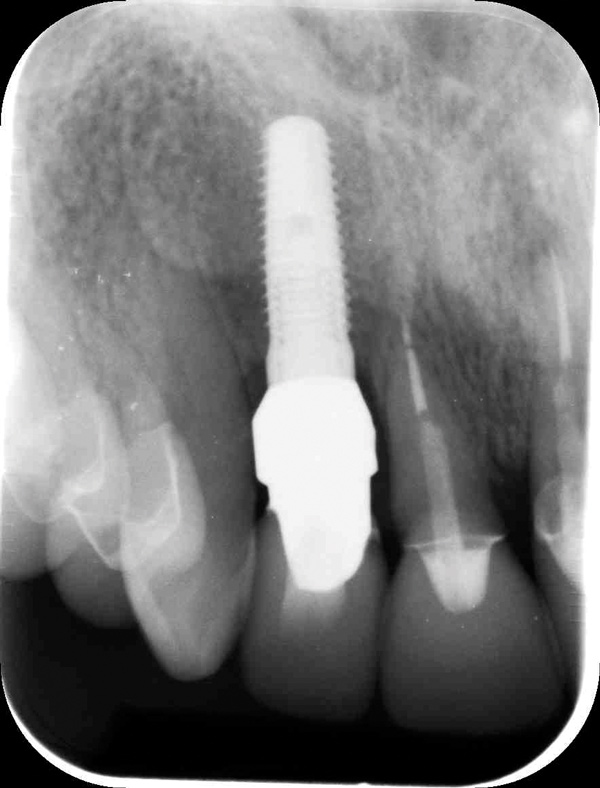

Fig 3. Initial buccal view of tooth No. 7.

Figure 3

To predict peri-implant esthetic outcomes, Kois described five essential diagnostic keys that need to be assessed before removing a periodontally hopeless tooth (Figure 3 and Figure 4): (1) relative tooth position; (2) form of the periodontium; (3) periodontal biotype; (4) tooth shape; and (5) position of the osseous crest. Failing teeth that have a thick, flat gingival biotype, are square shaped, and have < 3 mm vertical distance from the position of the facial and interproximal crest have the lowest risk of developing recessions after implant placement.23 Therefore, implant surgery may be performed by either an open flap or flapless approach. However, teeth with a thin soft-tissue biotype, a highly scalloped gingival architecture, and a triangular shape that are positioned facially have less-predictable peri-implant esthetic outcomes. When a tooth presents with these unfavorable anatomical features, grafting procedures should be considered both before and after tooth extraction to prevent vertical loss and facial collapse of the gingival architecture.21 Flapless tooth extraction should be attempted in the esthetic zone to maintain blood supply from the periosteum and endosteum and maximize healing potential (Figure 5).44 In addition, several surgical protocols have been proposed to avoid peri-implant mucosal recessions, including 3-dimensional implant positioning,45,46 the use of platform-switching implants,47,48 and soft-tissue augmentation.8,49,50